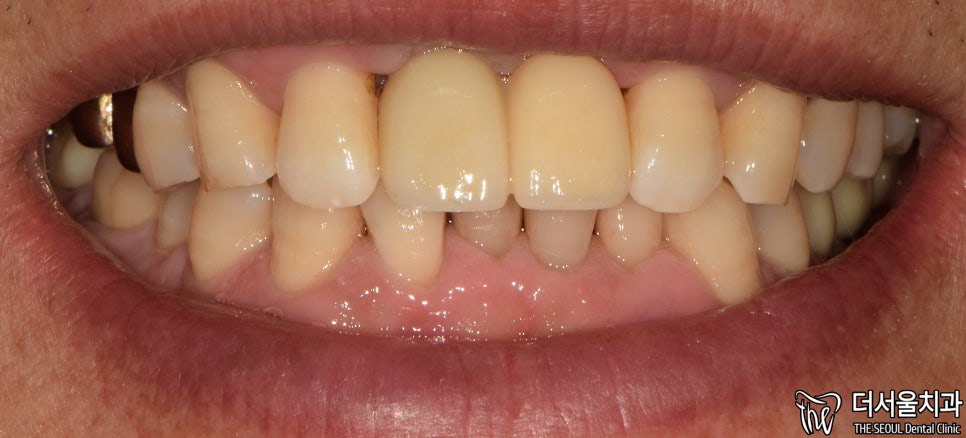

5. 완료

최종 완료된 모습입니다.

첫 진료 때보다 깔끔해졌죠?

치아와 비슷한 색으로 된

‘지르코니아’ 크라운을 씌워드렸는데요.

튼튼하다는 특징도 있어

많은 분께 선호되고 있는 재료입니다.

실제로 보면 이렇게

다른 치아와 크게 다르다는 점이 없죠?

환자분도 치료 결과에 만족스러워 하셨습니다.